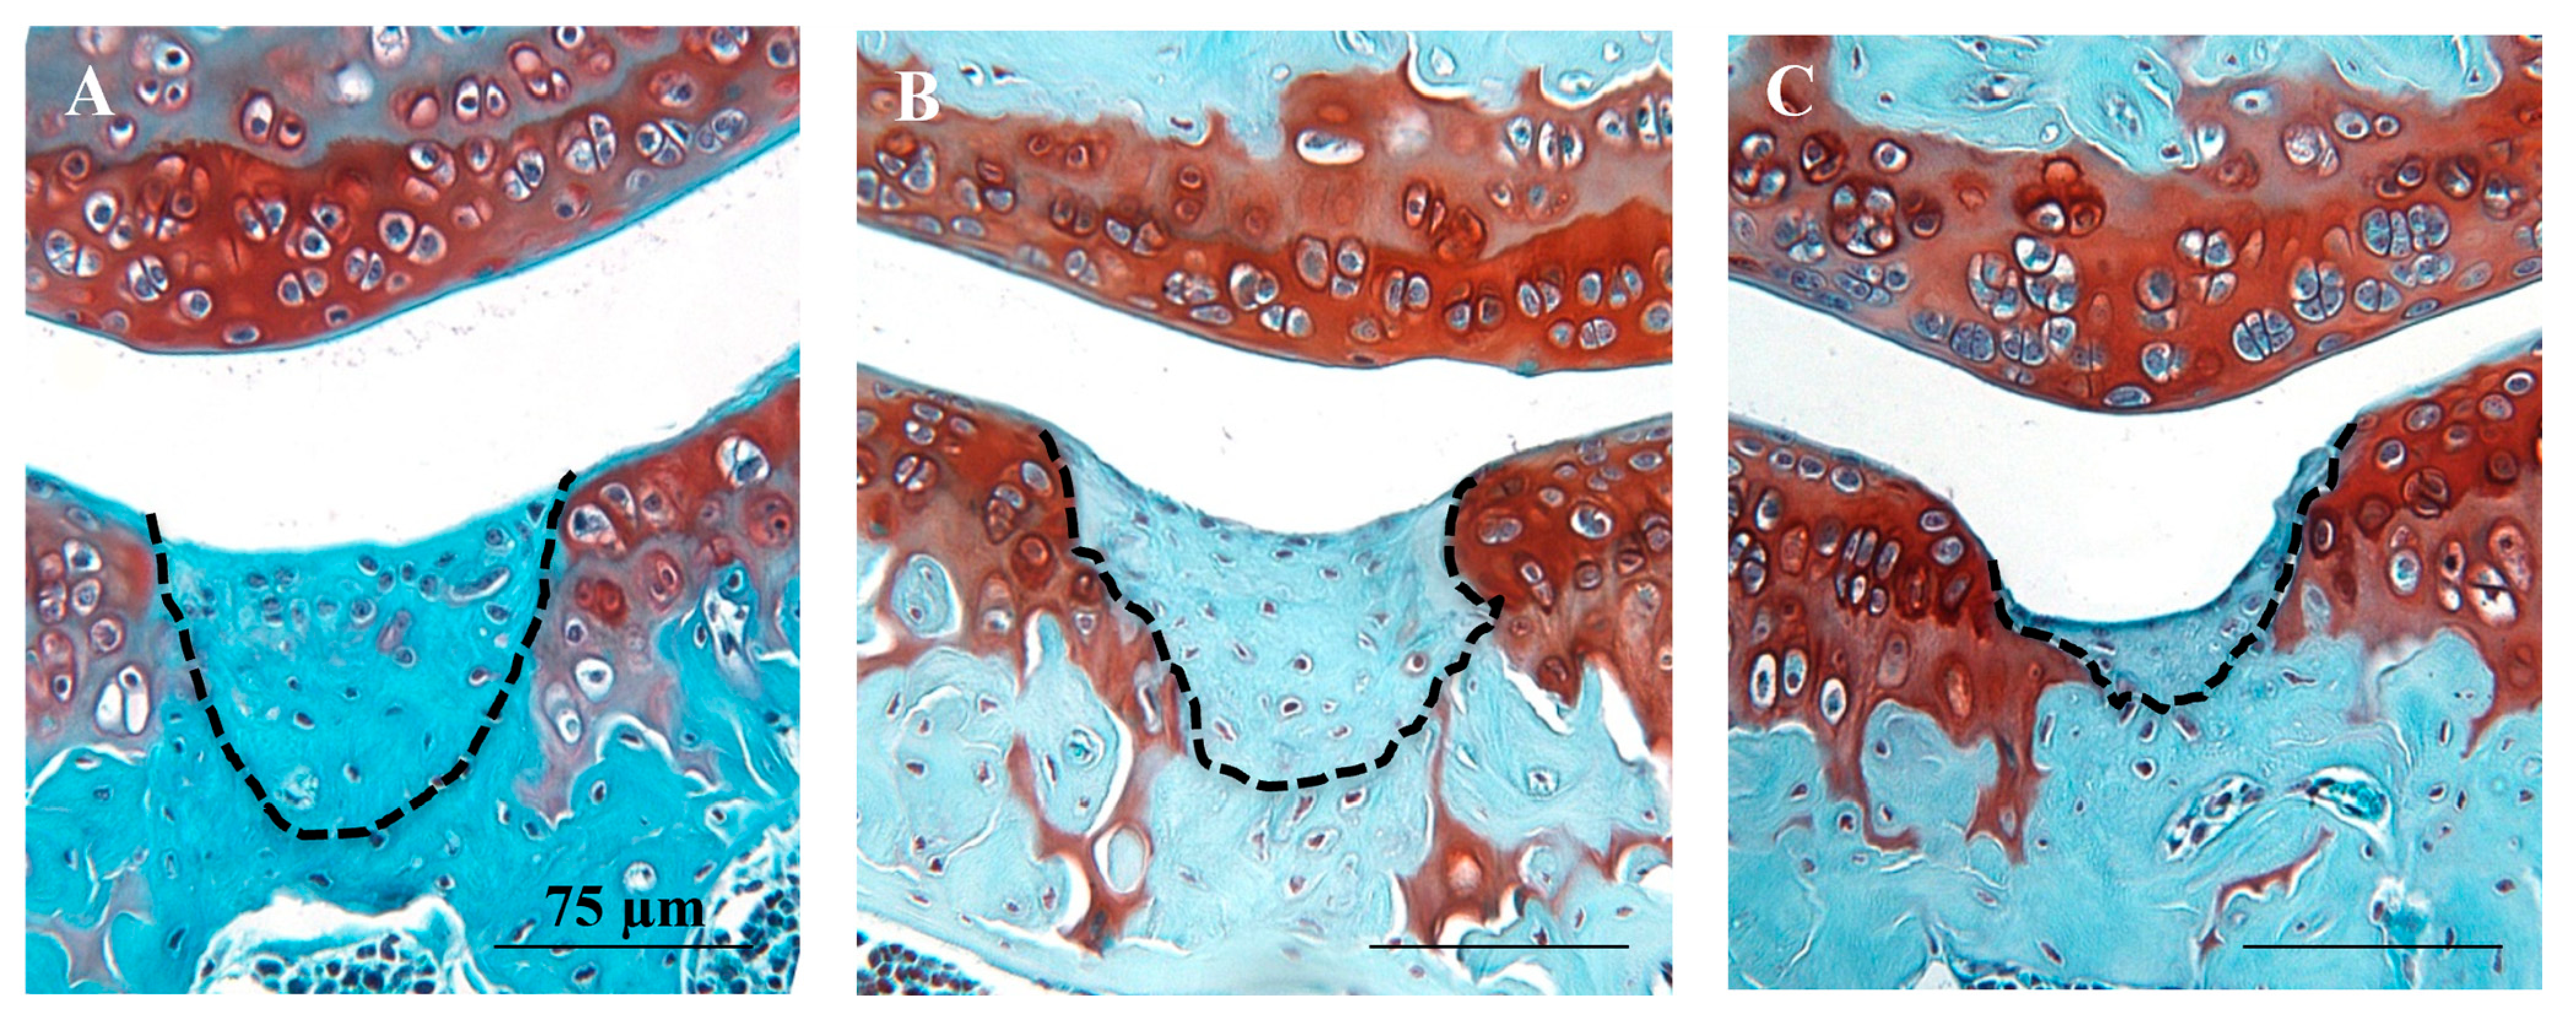

Analysis of cartilage repair in safranin O and fast green stained sections showed that both hMSC treatment groups had significantly lower mean Wakitani scores (i.e., better repair) compared to the vehicle group (p = 0.009 for hUC-MSCs and p = 0.006 for hBM-MSCs) (Figure 2 and Appendix A Figure A1). Furthermore, there was a low level of synovial hyperplasia but no overt signs of synovitis and no significant differences in synovitis scores between any of the treatment groups (no cells vs. hBM-MSCs p > 0.999; no cells vs. hUC-MSCs p = 0.826; hBM-MSCs vs. hUC-MSCs p > 0.999) (Figure 3). The inter-rater reliability (ICC) between scorers of the Wakitani cartilage repair score and synovitis score was 0.98 and 0.88, respectively and the intra-rater class reliability was 0.96 and 0.78.

Figure A1.

Cartilage formation and repair after joint surface injury. Safranin O and fast green stained sections from individual mouse knees showing the injury site in the patellar groove at 8 weeks post-injury in the sample groups (A) human UC-MSCs, (B) human BM-MSCs and (C) the control group (no cells injected). Clear repair tissue (indicated by dashed lines) can be seen in the MSC treated sections, whereas only minimal repair is present in the control group. Scale bars = 75 μm.